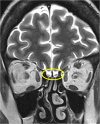

Medical imaging methods are assuming a greater role in the workup of patients with COVID-19, mainly in relation to the primary manifestation of pulmonary disease and the tissue distribution of the angiotensin-converting-enzyme 2 (ACE 2) receptor. However, the field is so new that no consensus view has emerged guiding clinical decisions to employ imaging procedures such as radiography, computer tomography (CT), positron emission tomography (PET), and magnetic resonance imaging, and in what measure the risk of exposure of staff to possible infection could be justified by the knowledge gained. The insensitivity of current RT-PCR methods for positive diagnosis is part of the rationale for resorting to imaging procedures. While CT is more sensitive than genetic testing in hospitalized patients, positive findings of ground glass opacities depend on the disease stage. There is sparse reporting on PET/CT with [18F]-FDG in COVID-19, but available results are congruent with the earlier literature on viral pneumonias. There is a high incidence of cerebral findings in COVID-19, and likewise evidence of gastrointestinal involvement. Artificial intelligence, notably machine learning is emerging as an effective method for diagnostic image analysis, with performance in the discriminative diagnosis of diagnosis of COVID-19 pneumonia comparable to that of human practitioners.